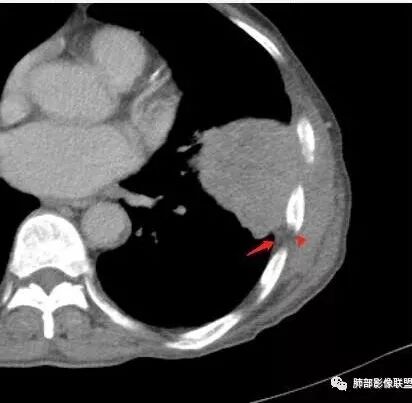

鳞癌,与吸烟关系密切,起源于支气管粘膜上皮,典型的征象就是支气管截断,周围型鳞癌往往体积较大,有时候与支气管关系不好判断,需要多平面重建看支气管的关系。

鳞癌因为侵袭性力较强,容易直接侵犯胸膜、胸壁,而周围型肺癌侵犯胸壁的90%癌肿是鳞癌,这也是鳞癌的一个特征性表现。邻近胸壁的脂肪层消失,胸壁肿块形成或有肋骨皮髓质边界不清的侵蚀破坏(而非边缘硬化或崩解)是瘤体向周围直接侵犯的可靠征象。

鳞癌因为破坏力强,其内可见灶样坏死区,坏死边界不清,其内血管破坏彻底。

肉瘤样癌也好发于中老年人,与吸烟关系密切。肿块体积往往较大,也是好发于胸膜下伴胸壁侵犯,也容易发生坏死,与周围型鳞癌的主要鉴别点在于支气管的关系和病灶内强化的情况。肉瘤样癌以环状强化为主,病灶周边多以癌组织为主,血供丰富,病灶中心区则以肉瘤成分为主,血供较差,易出现粘液样变性、坏死、出血,坏死边界清楚。